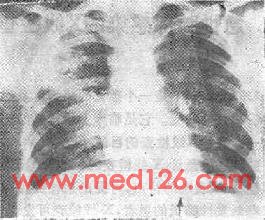

图112-2 右肺化脓性肺炎之X线表现

(五)空洞 见于肺化脓性感染,革兰阳性或阴性菌感染。实变区域之内出现空洞,空洞内可见到气液平面(图112-2)。